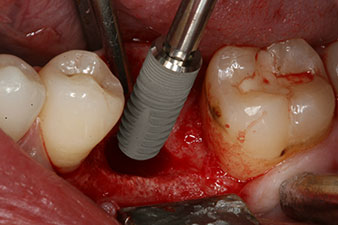

L’implant a été posé comme prévu après élimination complète du tissu de granulation (blueSky, bredent).

Le couple utilisé pour la pose guidée était de 43 Ncm.

En outre, après avoir vissé une tige de mesure (SmartPeg) spécialement conçue pour l'implant, la valeur ISQ a été mesurée à l’aide de la sonde du module W&H Osstell ISQ.

Ce module est fourni en option avec l’Implantmed de W&H et est fixé au moteur d’implantologie (cf. Fig. 11). La valeur ISQ adimensionnelle mesurée immédiatement après l’insertion était de 64 dans l’axe oro-vestibulaire et de 68 dans l’axe mésio-distal (valeur maximale = 100).

Ces valeurs auraient pu indiquer une cicatrisation ouverte, voire une restauration immédiate. Étant donné le volume osseux crestal insuffisant au niveau de l’implant, une augmentation osseuse a été pratiquée localement à l’aide des fragments osseux recueillis lors de la préparation du lit implantaire, et des points de suture effectués pour éviter le contact de la salive.